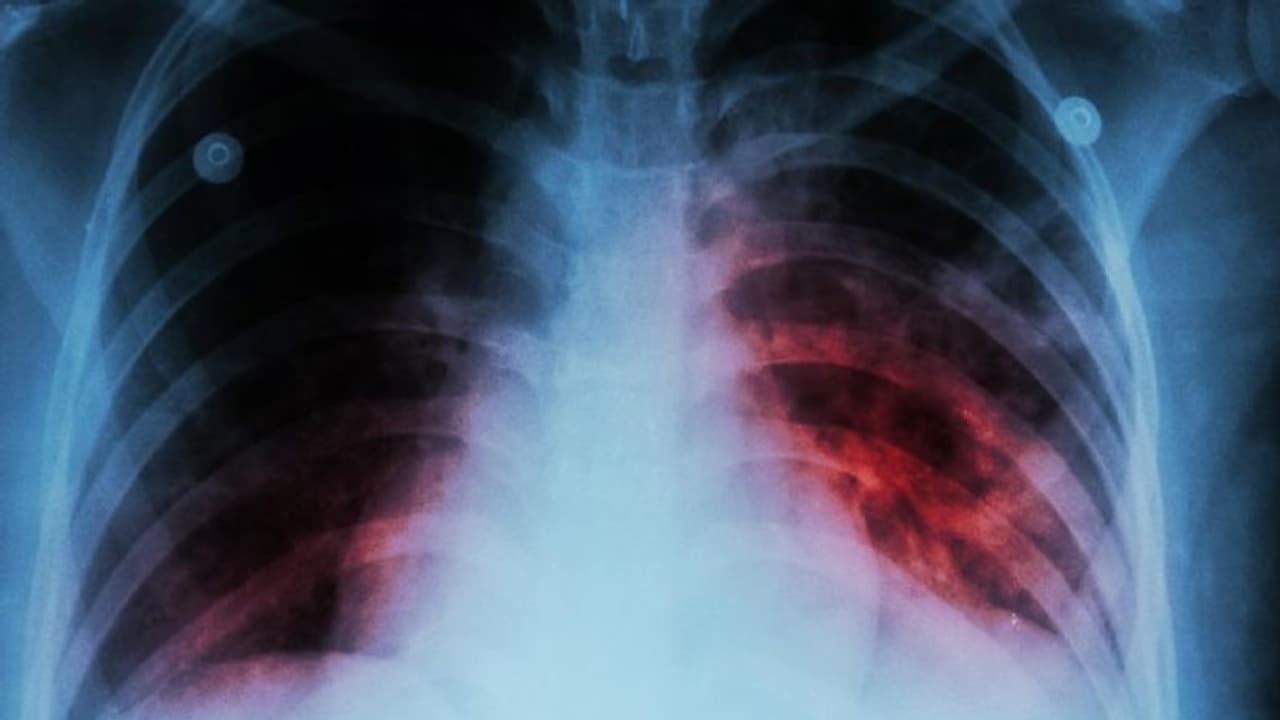

২০২৩ সালের গ্লোবাল টিউবারকিউলোসিস (টিবি) রিপোর্ট প্রকাশ করেছে বিশ্ব স্বাস্থ্য সংস্থা (WHO)। এই রিপোর্টেই দেখা গেল যে, কোভিড ১৯-এর পর থেকে টিবি মোকাবিলায় উল্লেখযোগ্য অগ্রগতি করতে পেরেছে ভারত। রিপোর্টে প্রকাশিত হয়েছে, ভারতের স্বাস্থ্য দফতর চিকিৎসা কভারেজে টিবি আক্রান্তের সংখ্যার প্রায় ৮০ শতাংশই নথিবদ্ধ করেছে, যা আগের বছরের তুলনায় উল্লেখযোগ্যভাবে ১৯ শতাংশ বৃদ্ধি পেয়েছে।

এই কারণে ভারতে যক্ষ্মা (Tuberculosis) রোগীর সংখ্যাও কমে গেছে। কঠোর প্রচেষ্টার কারণে যক্ষ্মা রোগ ২০১৫ সালের হারের তুলনায় ২০২২ সালে ১৬ শতাংশ কমে গেছে। এই হ্রাসের হার বিশ্বব্যাপী টিবি প্রকোপ হ্রাসের প্রায় দ্বিগুণ, যা ৮.৭ শতাংশে এসে দাঁড়িয়েছে। টিবি সম্পর্কিত মৃত্যুর হারও উল্লেখযোগ্যভাবে হ্রাস পেয়েছে, একই সময়ের মধ্যে ভারত এবং বিশ্বব্যাপী উভয় ক্ষেত্রেই ১৮ শতাংশ হ্রাস পেয়েছে যক্ষ্মায় মৃত্যুর হার।

ভারতে ২০২২ সালে, ২৪.২২ লক্ষেরও বেশি যক্ষ্মার কেস রিপোর্ট করা হয়েছিল, যা প্রাক-কোভিড স্তরকে ছাড়িয়ে গেছে। গুরুত্বপূর্ণ সরকারি উদ্যোগ, যেমন সক্রিয় কেস খোঁজা, ব্লক স্তরে চিকিৎসার সম্প্রসারণ, 'আয়ুষ্মান ভারত' স্বাস্থ্য ও সুস্থতা কেন্দ্রের মাধ্যমে স্ক্রিনিং পরিষেবা এবং বেসরকারি খাতের নিযুক্তিগুলি যক্ষ্মার কেস সনাক্তকরণে ব্যাপক সাহায্য করেছে।